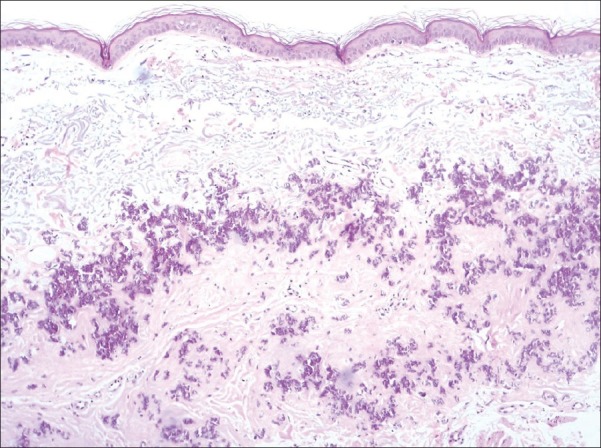

Dermatological examinations revealed lax skin and multiple yellowish colored papules, which coalesced to give a ‘plucked chicken skin’ appearance [Figure 1]. No other sites were involved. Skin biopsy of samples from the neck revealed fragmentation and calcification of the connective tissue fibers in the middle and lower third of the dermis, with H and E stain [Figure 2]. Von-Verhoeff-Van Gieson stain confirmed the diagnosis. No angioid streaks of the retina were seen. Gastroenteroscopy, 2D echo and chest X-ray revealed no abnormality.

Figure 2.

Biopsy showing fragmentation of collagen fibers in middle and lower third of dermis